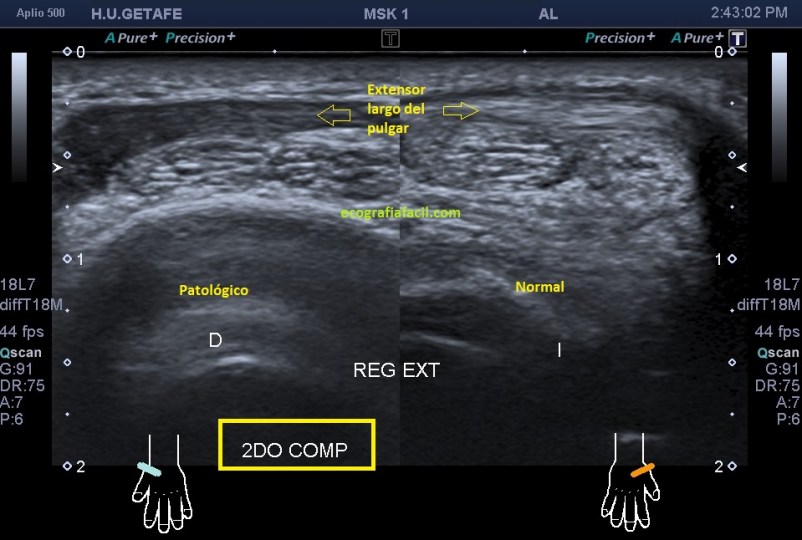

En esta imagen quiero que te fijes en el segundo compartimento y como el extensor largo del pulgar pasa por encima, los dos tendones del compartimento dos cortados en eje corto y el del tercero, cortado, pero en un corte para-axial. Lo importante es que te fijes en la ecogenicidad de ELP, en la izquierda hiperecogénico, isoecogénico con el segundo compartimento, por tanto normal. En la derecha hipoecogénico y más gordo, patológico.